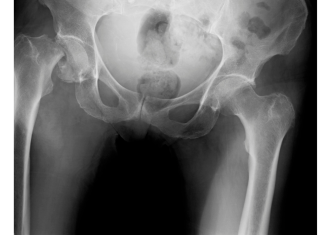

Fratture acetabolari e pelviche e ritorno allo sport

Le fratture acetabolari e pelviche rappresentano una sfida clinica rilevante nei pazienti in età lavorativa e fisicamente attivi. Il ritorno allo sport...